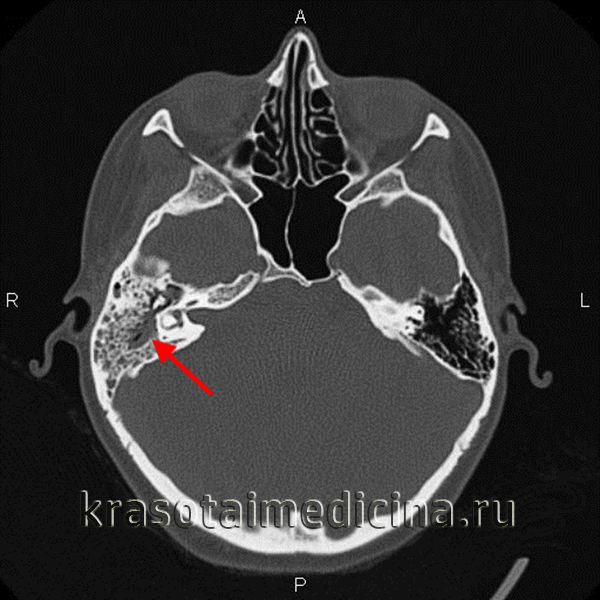

КТ височных костей. Деструкция сосцевидного отростка, сосцевидной пещеры, пирамиды и среднего уха правой височной кости, обусловленная холестеатомой